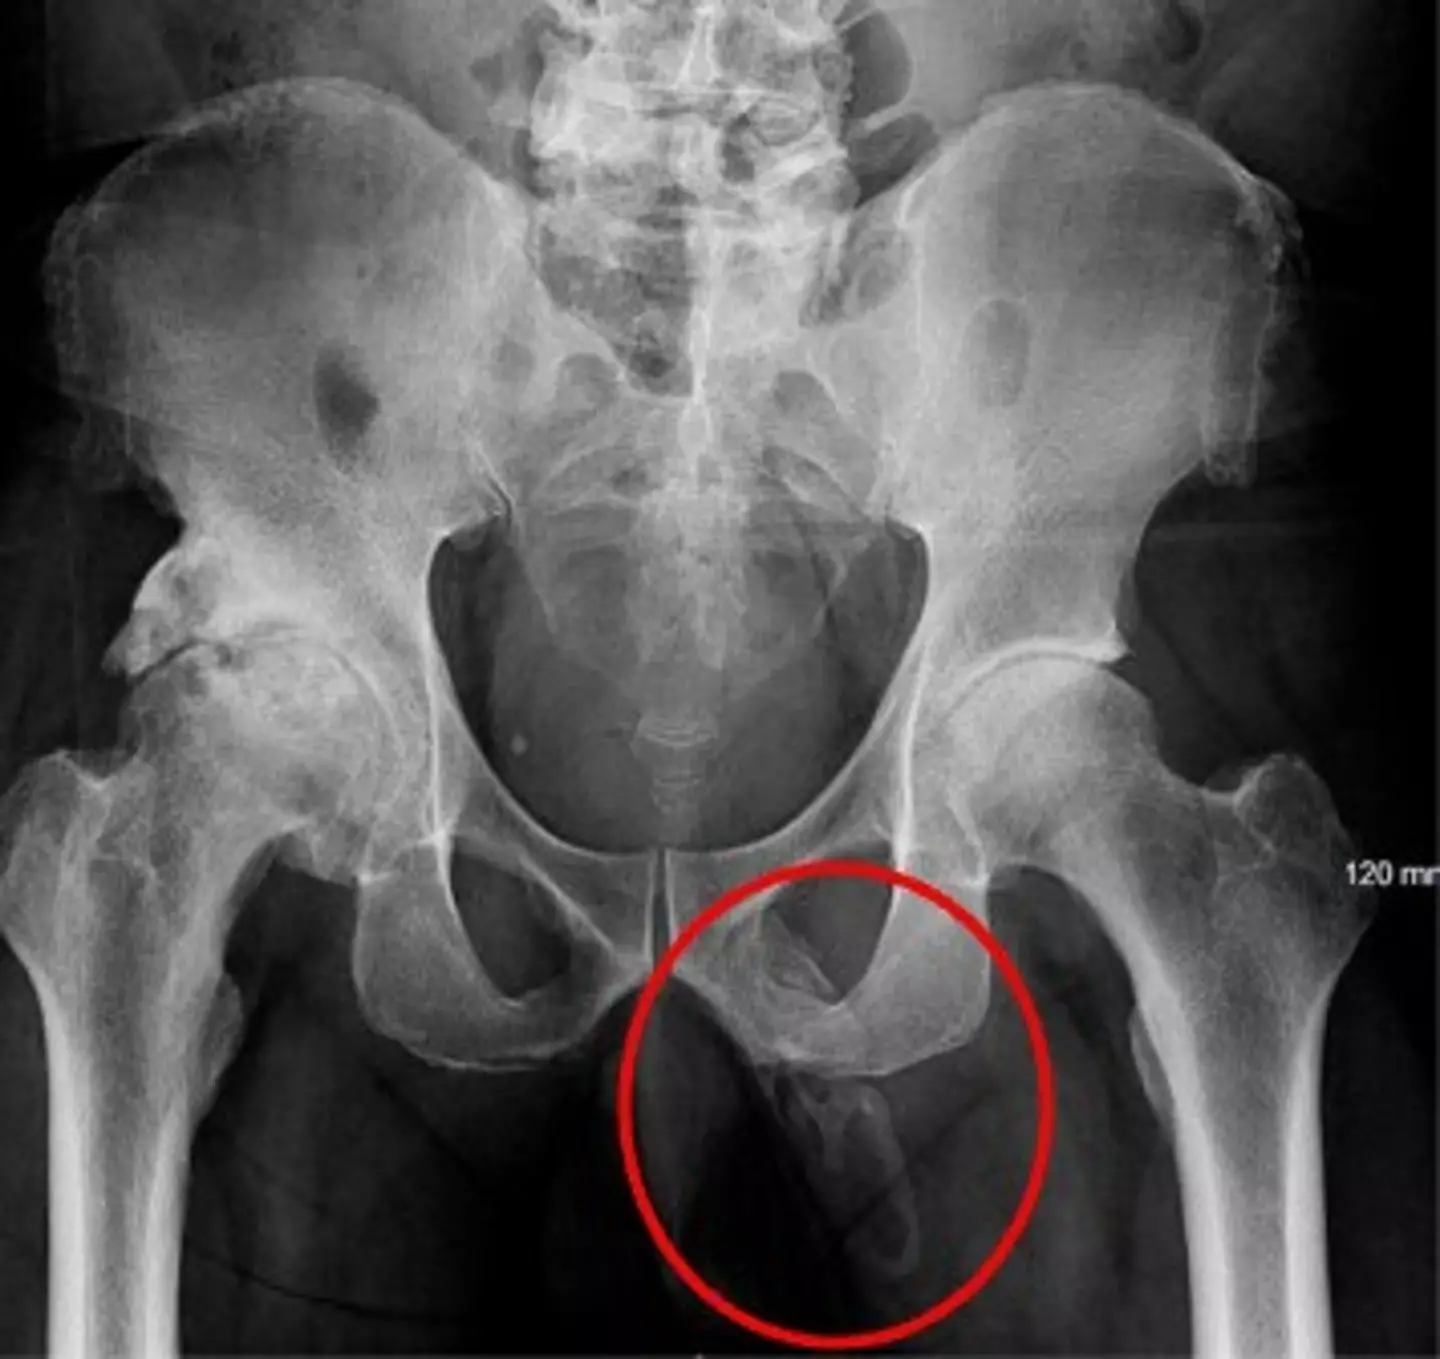

As per the Urology Case Report, the man's 'physical exam was negative except for a penile pain', sparking him to undergo an x-ray 'to rule out any fracture showed a severe, asymmetric degenerative changes of the right hip'.

But doctors discovered something unexpected when the results of the scan came back, and it turned out it had nothing to do with the man's hip.

The patient went on to be diagnosed with penile ossification - an extremely rare condition with fewer than 40 cases reported.